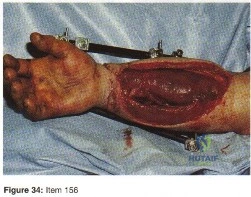

- Sural artery island flap.

- Free rectus abdominis flap.

- Extensor digitorum brevis flap.

- Staged cross leg flap.

- Split-thickness skin graft.